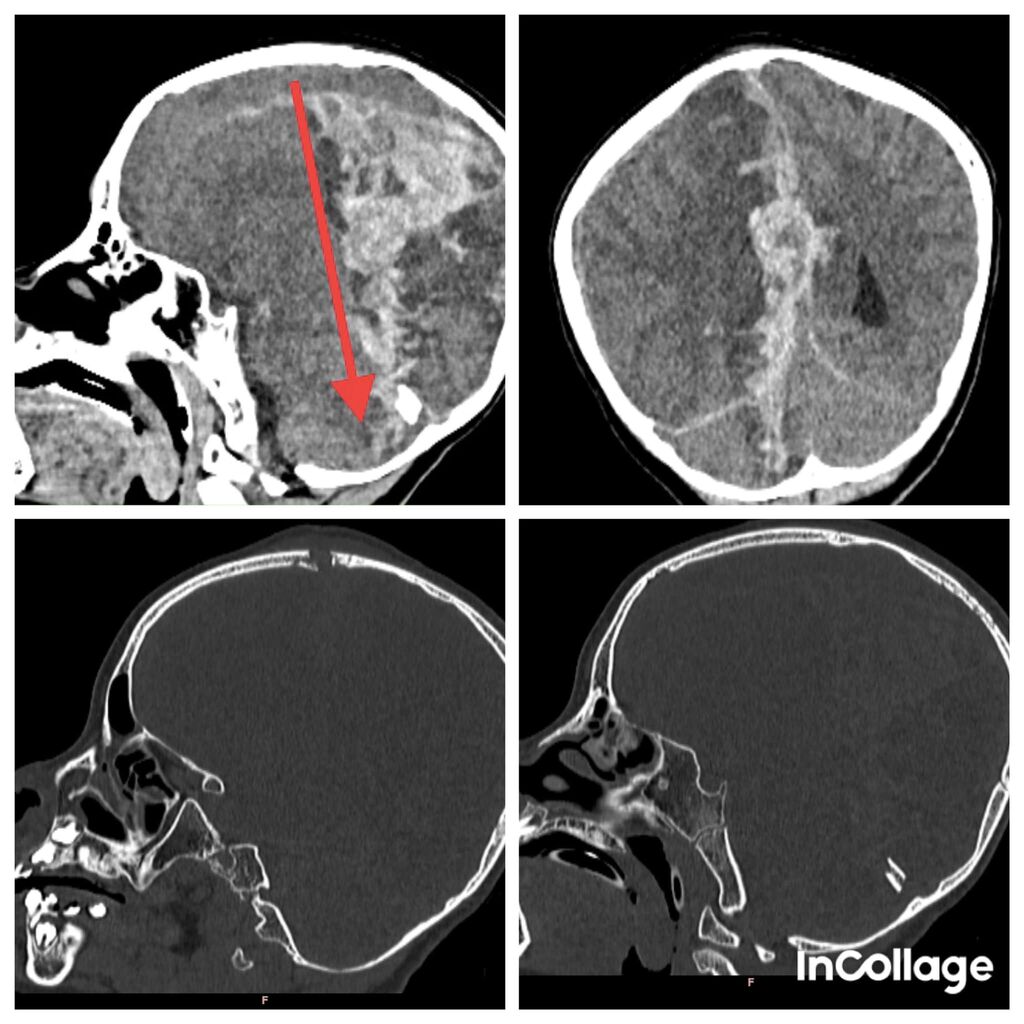

| Les films de scanners de tête de B.T.Y.N |

Les résultats du scanner ont montré une blessure importante au cerveau, provoquant d'importantes hémorragies sous-durales et intracérébrales, une compression et un œdème cérébral. L’enfant a été transféré ensuite à l'hôpital pédiatrique numéro 2 de Hô Chi Minh-Ville, et l'équipe médicale a immédiatement procédé à une intervention chirurgicale d'urgence pour retirer l'hématome et ouvrir le crâne pour le décompresser.

"Même s'il y a des signes de guérison, il y aura certainement des séquelles neurologiques car le cerveau a été gravement endommagé, le bébé ne peut pas encore parler et est encore faible dans la moitié gauche de son corps", a ajouté M. Doanh.